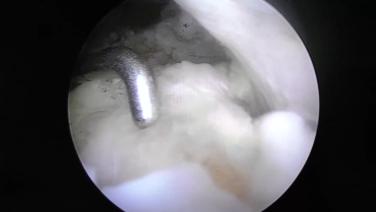

Radial Meniscal Tear: Featuring TRUESPAN Meniscal Repair System with William Arroyo, MD

TRUESPAN Meniscal Repair System with Amir Moinfar, MD